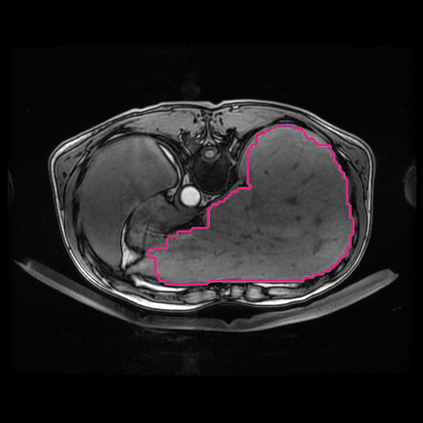

Radiomics uses quantitative medical imaging features to predict clinical outcomes. Currently, in a new clinical application, finding the optimal radiomics method out of the wide range of available options has to be done manually through a heuristic trial-and-error process. In this study we propose a framework for automatically optimizing the construction of radiomics workflows per application. To this end, we formulate radiomics as a modular workflow and include a large collection of common algorithms for each component. To optimize the workflow per application, we employ automated machine learning using a random search and ensembling. We evaluate our method in twelve different clinical applications, resulting in the following area under the curves: 1) liposarcoma (0.83); 2) desmoid-type fibromatosis (0.82); 3) primary liver tumors (0.80); 4) gastrointestinal stromal tumors (0.77); 5) colorectal liver metastases (0.61); 6) melanoma metastases (0.45); 7) hepatocellular carcinoma (0.75); 8) mesenteric fibrosis (0.80); 9) prostate cancer (0.72); 10) glioma (0.71); 11) Alzheimer's disease (0.87); and 12) head and neck cancer (0.84). We show that our framework has a competitive performance compared human experts, outperforms a radiomics baseline, and performs similar or superior to Bayesian optimization and more advanced ensemble approaches. Concluding, our method fully automatically optimizes the construction of radiomics workflows, thereby streamlining the search for radiomics biomarkers in new applications. To facilitate reproducibility and future research, we publicly release six datasets, the software implementation of our framework, and the code to reproduce this study.

翻译:放射科使用定量医学成像特征来预测临床结果。目前,在一个新的临床应用中,通过一个超常试验和高压过程,通过人工操作,从广泛的现有选项中找到最佳放射法。在本研究中,我们提议了一个框架,自动优化每个应用程序的放射工作流程的建设。为此,我们将放射作为模块工作流程,并包括每个部件的大量通用算法。为了优化每个应用程序的工作流程,我们使用随机搜索和聚合的自动机学习方法。我们用12种不同的临床应用来评估我们的方法,结果在曲线下应用的以下领域:1) 脂色瘤(0.83);2) 脱氧型纤维瘤(0.82);3 初级肝脏肿瘤(0.80);4 气肠肿瘤(0.77)、5 彩虹肝脏移植(0.61); 6 脑膜细胞变异常(0.45); 7) 肝细胞变异常(0.8) 脑纤维变异位(0.80); 9) 直径直线型癌症(0.74) 和头型癌症(0.77) 直径研究(10) 。